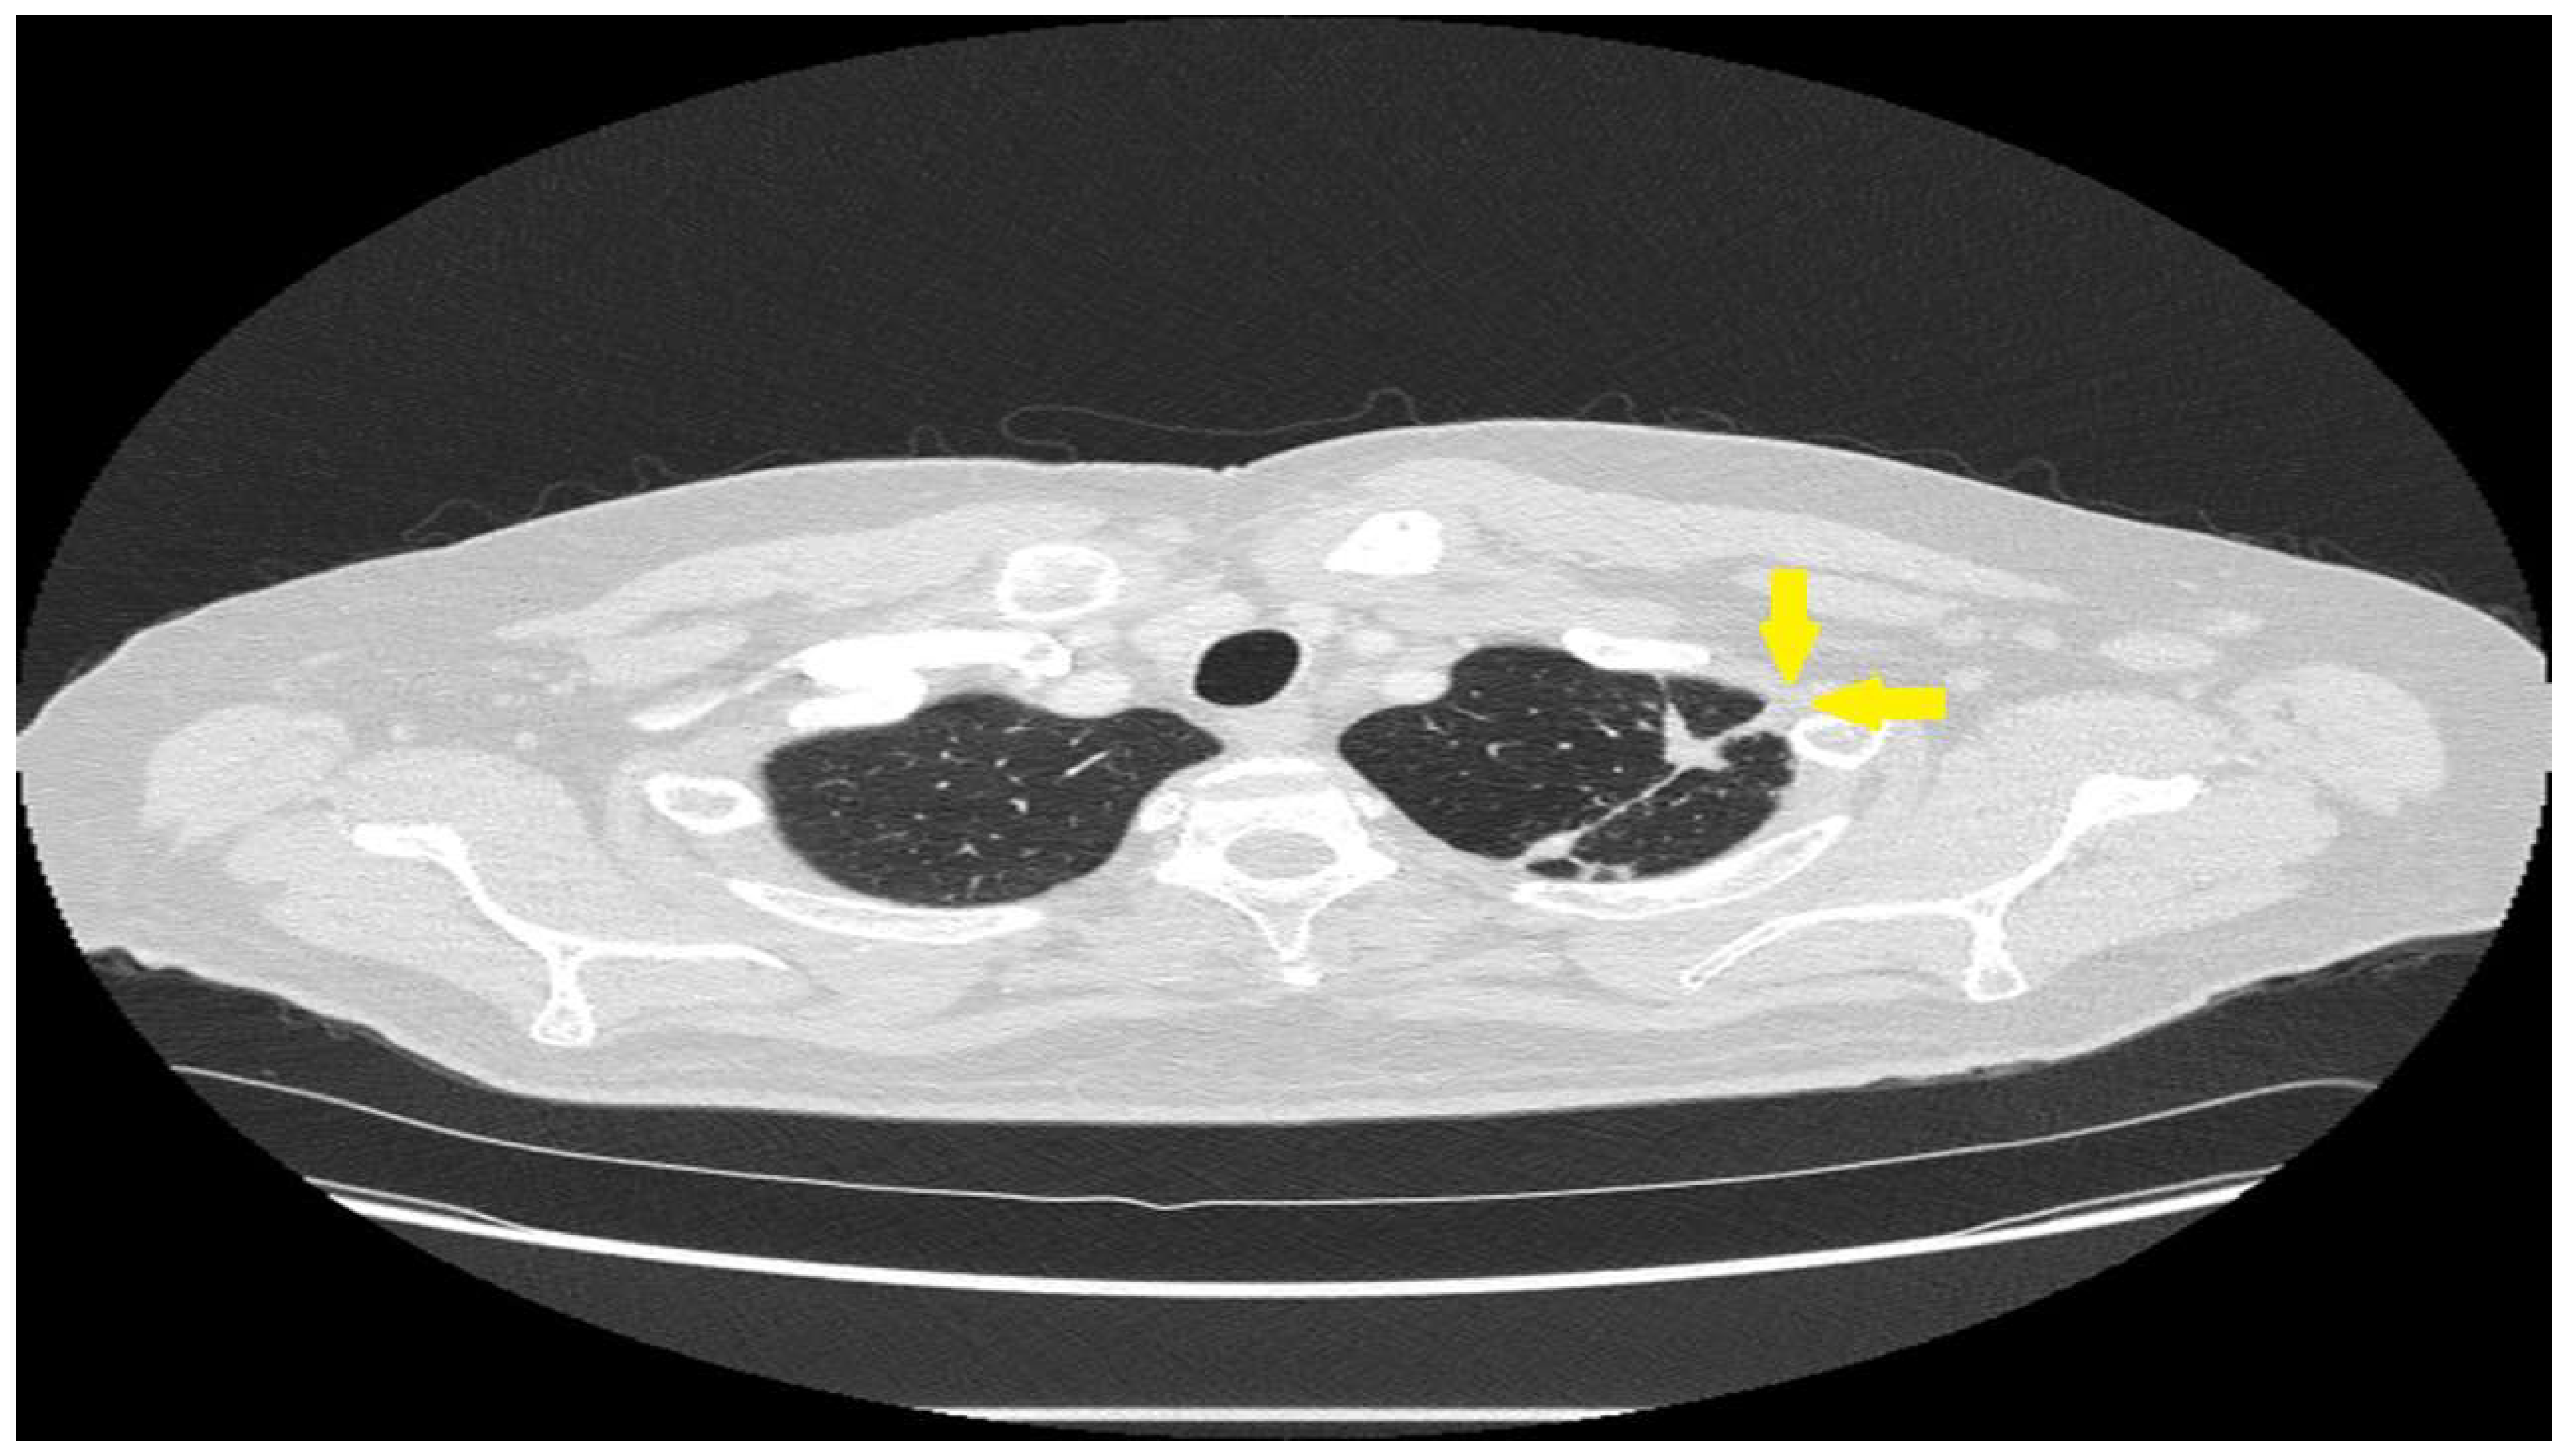

| Bronchiectasis | Fibrocystic sarcoidosis | Bronchiectasis from airway fibrosis from previous granulomatous inflammation. Hemoptysis from infectious bronchitis/bronchiectasis |

| Aspergilloma/Chronic aspergillus lung infection | Fibrocystic sarcoidosis | Aspergillus colonization of devitalized lung with subsequent locally invasive disease |